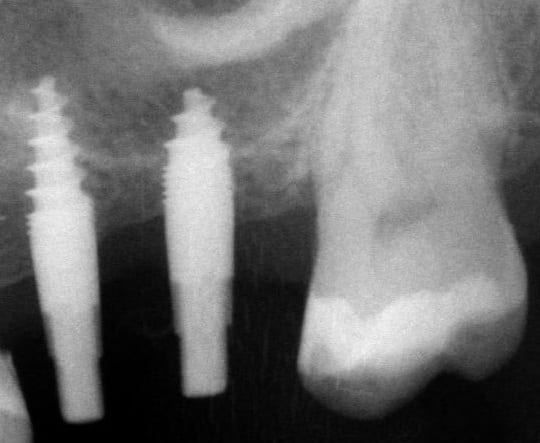

je voulais parler de ce fact pour les implants courts:minimum 4mm os vertical peut suffire (pour eviter un sinus lift externe de tatum) . dans ma pratique depuis quelques années je vois que ca marche , quelques cas cliniques des années passées.

j´ai oublié : 4mm plus 2mm( gagnés par un sinus lift interne)

La forme de ces implants ne me semble pas très adaptée pour soulever la membrane sans la perforer.

Je préfère dans ses cas, avoir un implant dont le bout est plat, et non agressif. Je pense qu'il y a un consensus pour dire que jusqu'à 2mm dans le sinus on risque pas grand chose.

oui effectivement c est preferable des implants pas agressifs, sur la photo 7 on se rends plus compte que la pointe est plate...

Le plus important dans un implant sont les 4 premiers millimètres crestales ( c'est pourquoi de nombreuses industries, NB, astra,Bio horizon... ont chosit de faire des implants avec des micro fissures crestales pour augmenter la surface sur ces premiers millimètres et garantir une meilleure stabilité 1aire et 2aire).La partie dans l'os spongieux est moins décisive. Dans un contexte comme celui ci le platform switching est un facteur à ne pas négliger.